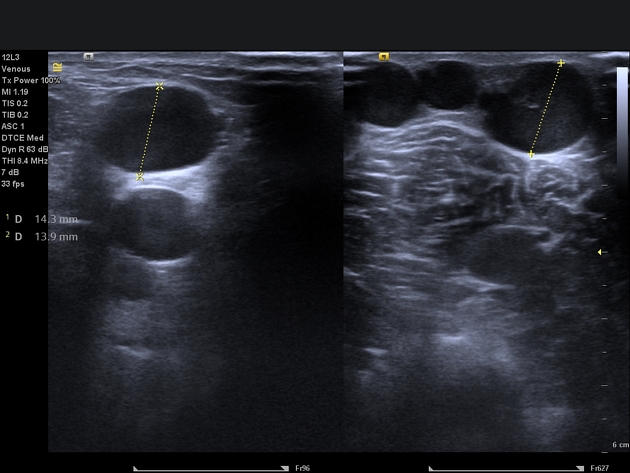

В серошкальном режиме визуализируется расширение просвета подкожных и перфорантных вен с утратой нормального венозного калибра, неравномерностью стенок и их извитостью, что свидетельствует о хронической венозной недостаточности.

- Диаметр варикозно изменённых вен, что даёт возможность определить степень венозной дилатации и необходимость вмешательства.